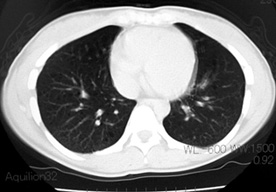

LAM患者さんに認められた両側肺気腫(右図:胸部CT)

firstCT.jpg

初診時CT(左)から2年後のCTでは肺の嚢胞化が著明となっている。